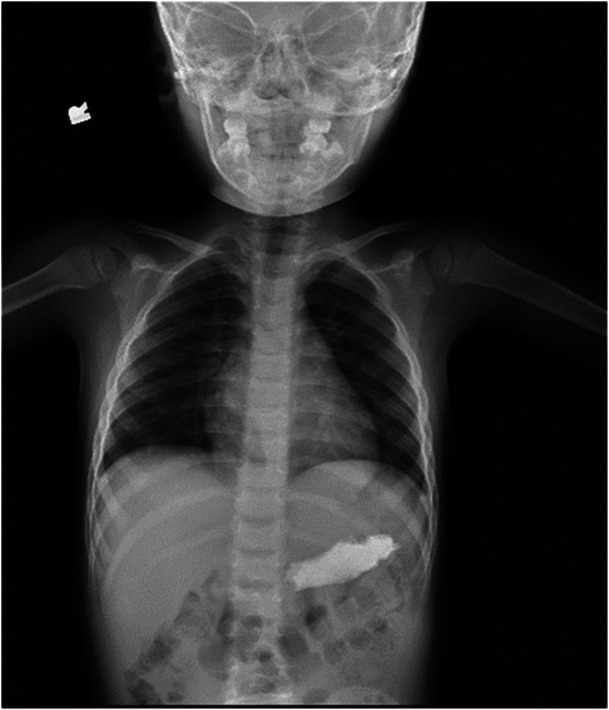

Kinetic magnetic sand, composed of ultra-fine sand and dimethicone in a 98%-2% ratio, is a versatile sensory toy known for its moldable properties and structural stability (1). Despite the name, it lacks actual magnetic features. Ingesting kinetic sand can pose risks, including choking and gastrointestinal issues, especially in young children. This case report details a unique incident involving a 3-year-old who ingested a significant amount of kinetic sand. Although the sand's ingredients are generally hypoallergenic and nontoxic, its grainy texture presented challenges for retrieval. The patient was closely monitored, and ultimately, the sand passed without complications. While no official guidelines exist for managing such cases, individual assessments, considering factors such as ingestion time, symptoms, and age, are crucial for determining the appropriate course of action, which may range from observation to more invasive procedures like endoscopy or surgery.